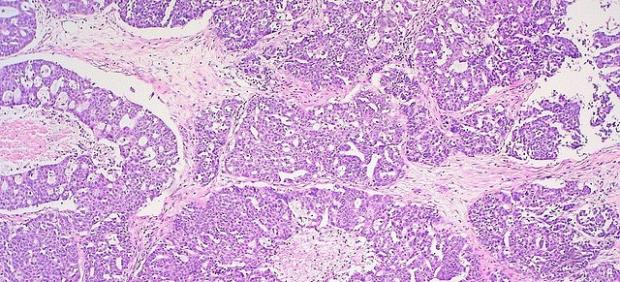

Según explica el doctor Curtis McCloskey, «la fibrosis ocurre cuando los tejidos corporales se lesionan e inflaman repetidamente, dejando fibras de colágeno duras que se acumulan con el tiempo, como una cicatriz en la piel«, y añade «a las células cancerosas les gusta crecer en estos tejidos fibróticos». McCloskey es el autor principal del estudio, y realizó la investigación mientras era estudiante de doctorado en el laboratorio de la doctora Barbara Vanderhyden en el Hospital de Ottawa (Canadá).

El equipo descubrió que la fibrosis de los ovarios es una parte normal del envejecimiento, que generalmente aparece después de la menopausia. Durante su investigación, el doctor McCloskey, becario postdoctoral en el Centro de Cáncer Princess Margaret, se sorprendió al encontrar un ovario de una mujer de 69 años que no tenía fibrosis. Los registros médicos mostraron que había estado tomando metformina, un medicamento para la diabetes tipo 2.

Los investigadores realizaron entonces una serie de experimentos para investigar los vínculos entre la fibrosis ovárica, el envejecimiento y la metformina. En primer lugar, querían saber qué estaba causando la fibrosis, y pensaron que la respuesta podría estar en la ovulación, ya que, cuando un ovario libera un óvulo, se inflama y crea un ciclo mensual de herida y reparación.